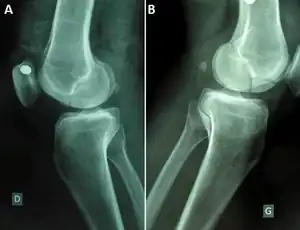

| Segond fracture | Paul Segond | lateral tibial plateau avulsion fracture with anterior cruciate ligament tear | Segond fracture at Who Named It? | ||

| Stieda fracture | Alfred Stieda | avulsion fracture of the medial femoral condyle at the origin of the medial collateral ligament | Stieda's fracture Archived 2022-05-17 at the Wayback Machine at TheFreeDictionary.com | ||